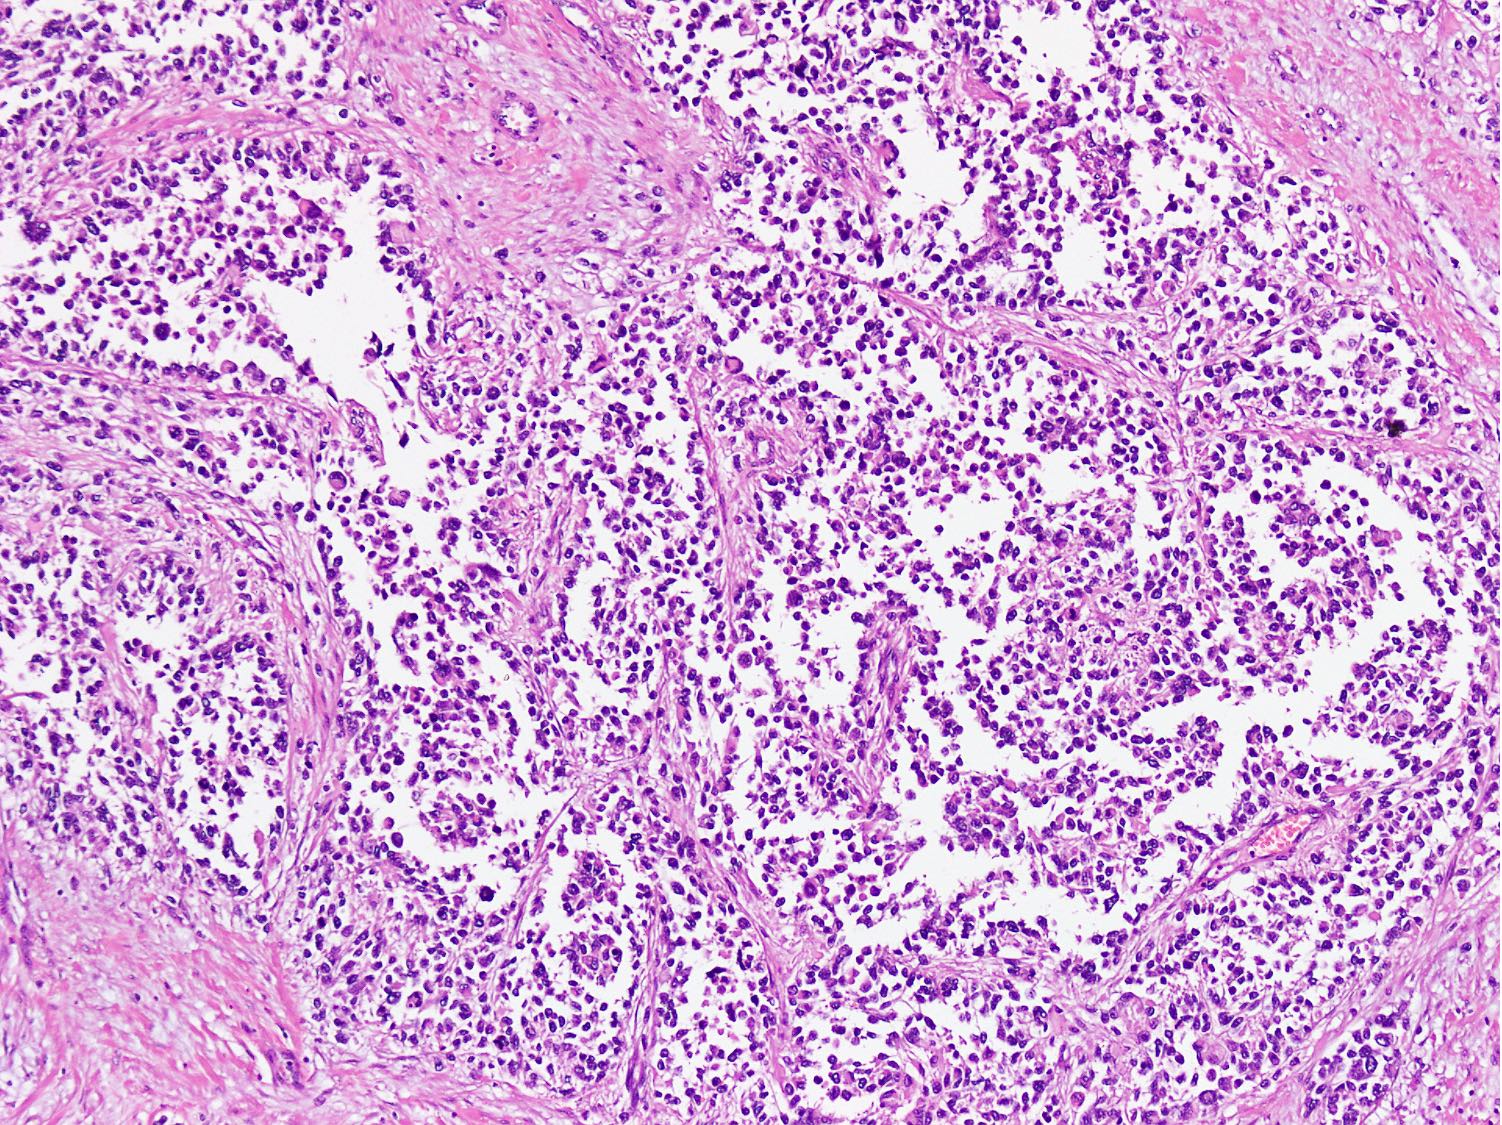

Microscopic (histologic) description

- Cellular round cell tumor

- Large clusters, nests, cords and trabeculae of primitive round cells, separated by variably thick fibrovascular septa

- Loss of cellular cohesion in the center forms alveolar-like, cystic and vague papillary appearance (Histopathology 2022;80:98)

- Layer of cells adheres to the periphery of the spaces and fibrous septa

- Small to intermediate sized monomorphic cells with scant cytoplasm

- Hyperchromatic nuclei with variable conspicuous small nucleoli

- Cells in the center have poor preservation and are necrotic; may appear floating

- Multinucleated tumor giant cells with wreath-like lineup of nuclei are common (Acta Pathol Microbiol Immunol Scand A 1982;90:345)

- Round to oval rhabdomyoblasts with abundant acidophilic cytoplasm may be present

- Brisk mitosis and variable tumor necrosis

Microscopic (histologic) images

Contributed by Nasir Ud Din, M.B.B.S.